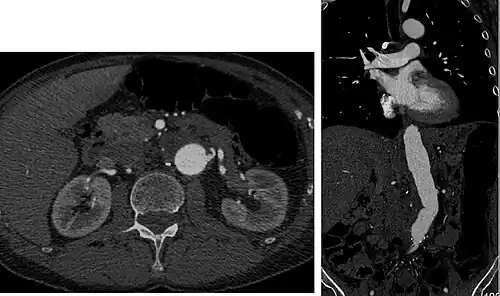

Sagittal thin slice of a computed tomography angiography abdominal aortic aneurysm (AAA) (arrows) | |

Aorta and great arteries

CTA can be used in the chest and abdomen to identify aneurysms in the aorta or other major blood vessels. These areas of weakened blood vessel walls that bulge out can life-threatening if they rupture. CTA is the test of choice when assessing aneurysm before and after endovascular stenting due to the ability to detect calcium within the wall.[3] Another positive of CTA in abdominal aortic aneurysm assessment is that it allows for better estimation of blood vessel dilation and can better detect blood clots compared to standard angiography.[4]